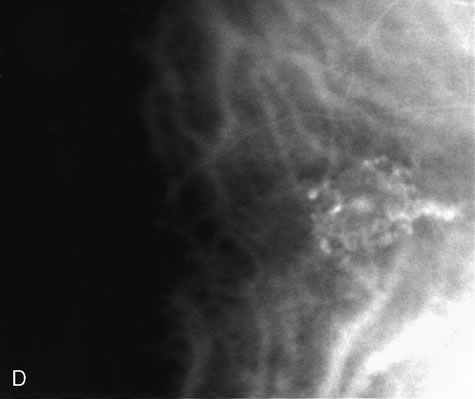

Fig. 29. 14-year-old adolescent girl with sudden loss of vision in the left eye to 20/400. A. Clinical photograph of the posterior pole demonstrates a neurosensory macular detachment simulating central serous chorioretinopathy. B. Composite fundus photograph of the same eye demonstrates the presence of a localized area of retinal capillary telangiectasia in the temporal periphery. The intraretinal yellowish material is consistent with dehemoglobinized blood. There are also intraretinal exudates scattered throughout the fundus. C. Composite fluorescein angiogram of the same eye reveals diffuse retinal capillary telangiectasia and intraretinal leakage. The dilated retinal telangiectatic vessels are actively leaking and are responsible for the macular neurosensory detachment. This patient was diagnosed with Coats' disease. D. Scatter laser photocoagulation of the telangiectatic vessels was carried out.